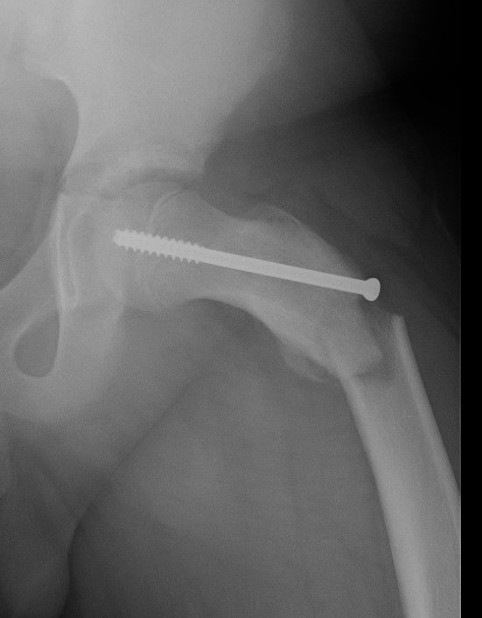

Subtrochanteric fracture

Subtrochanteric fracture likely causes by multiple drill holes / attempts

Cause

Too low screw entry

Multiple drill holes to get correct entry

Management

Intramedullary nail